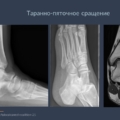

Таранно-пяточная коалиция:

Врожденное сращение.

Рентген-признак: «С-знак» на боковой проекции.

КТ: «золотой стандарт» для оценки костной коалиции.